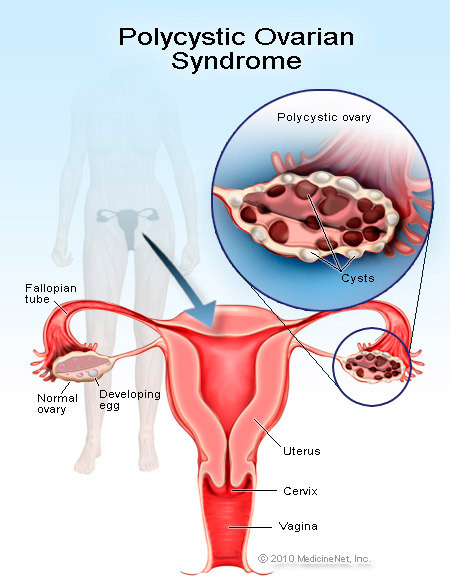

يلجأ للمركز العديد من النساء للتلخص من هذه الظاهرة التي تلازم النساء العربيات اكثر من غيرهن، تتلخص اعراض هذه الظاهرة في عدم انتظام الدورة الشهرية او انقطاعها، ارتفاع نسبة هرمون الذكورة (Testosterone) الذي يؤدي الى ظهور بثور الوجه Acne وتزايد نمو الشعر في الوجه، البطن، الصدر والارجل، افراط في السمنة وسقوط شعر الرأس، قلة تحسسهن لهرمون الانسولين واخيراً صعوبة في الانجاب.

نقوم في المركز بإجراء الفحوصات الهرمونية اللازمة ومعالجة كافة الظواهر الاخرى مع التشديد على فقدان الوزن واعطاء الادوية الخاصة لتنظيم الدورة وتحسين الاباضة بالاضافة الى معالجة مشكلة الانجاب بالطريقة السالفة الذكر وهي تقنية انضاج البويضات خارج الجسم (IVM).